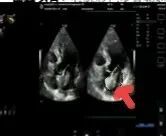

2025年深秋的一個清晨,82歲的馬奶奶(化名)因持續胸悶氣短被家人送至醫院心內科。心臟超聲檢查顯示,她的左心房內有一個直徑近5厘米的腫瘤,隨心跳規律擺動,如同一個隨時可能破裂的“不定時炸彈”。更危急的是,冠脈造影進一步揭示其冠狀動脈多支血管嚴重狹窄,左前降支狹窄達95%,回旋支中段完全閉塞,右冠狀動脈彌漫性病變—兩種致命性心臟疾病的疊加,讓這位高齡患者的生命岌岌可危。

術前超聲